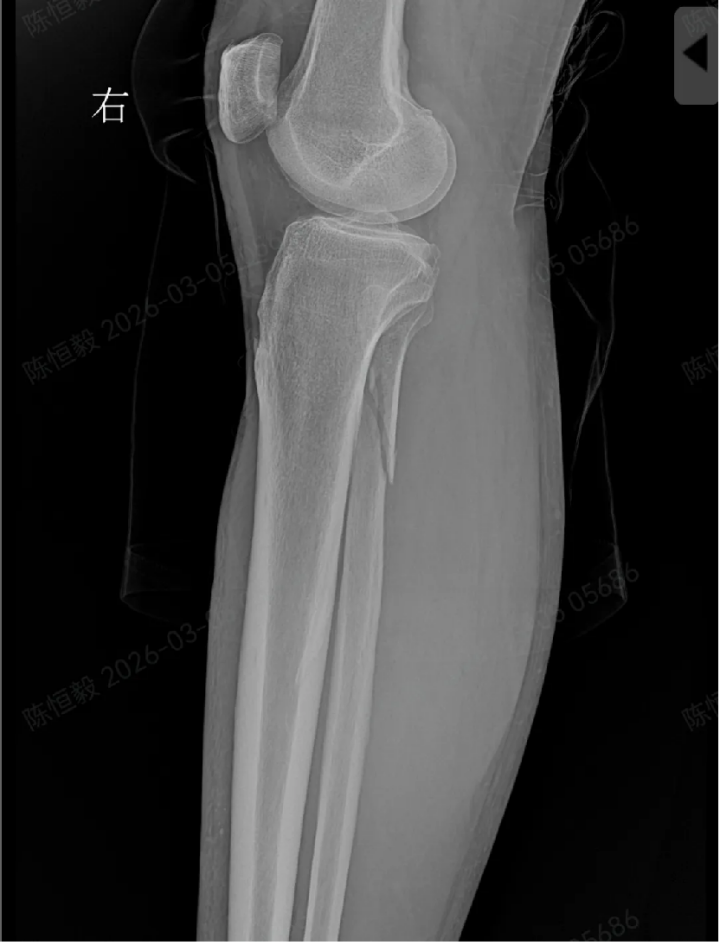

在北京积水潭医院郑州医院拍 X 光片后未见明显骨裂,王大爷更是觉得无需治疗,准备回家自行休养。但接诊的足踝外科主任杨建义查看片子并仔细为其体格检查后,发现了异常,当即告知王大爷,其下胫腓部位大概率存在损伤,建议住院做进一步详细检查,排除隐匿性问题。

王大爷听从建议住院后,经完善体格检查及 CT 检查,最终确诊为复杂的 Maisonneuve 骨折:不仅存在下胫腓分离,还合并前踝 Chapute 结节撕脱骨折、后踝骨折、内踝骨折,同时伴有腓骨高位骨折。